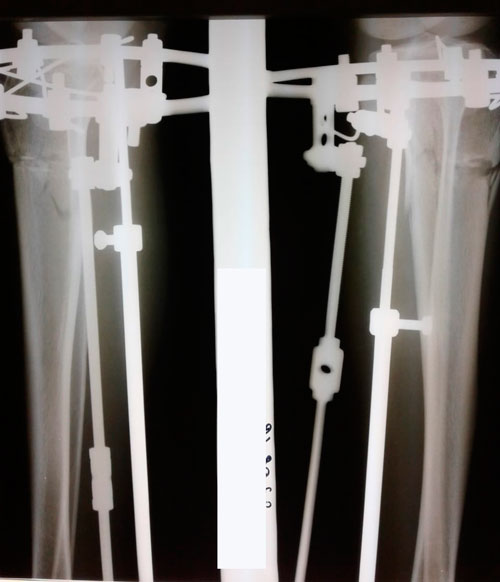

Ножки на сращении.

Дата операции 06.08.2018г.

Дата снятия аппаратов - 31.10.2018г.

Срок сращения - 84 дня.